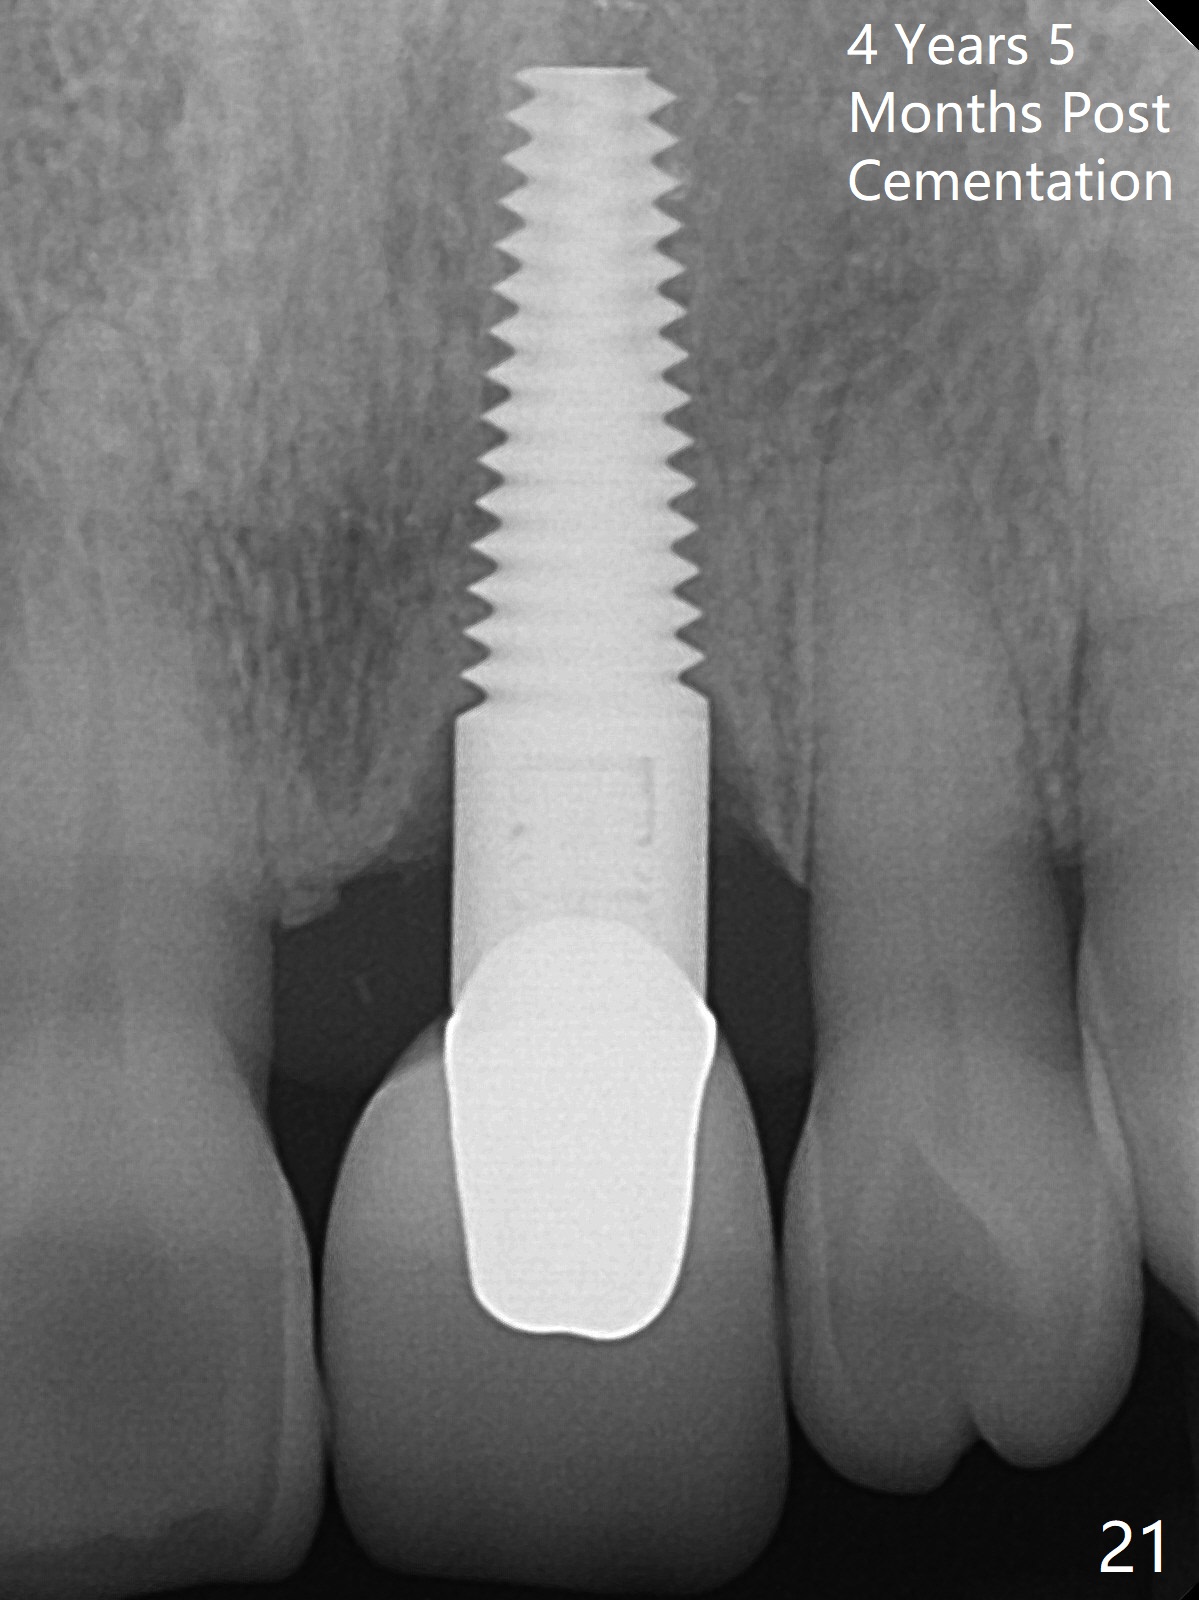

A 60-year-old lady had an abscess mesial to #9 six years ago (Fig.1,2 <), treated as a perio lesion by laser (Fig.3) and osseous surgery without bone graft (Fig.6, followed by CT exam revealing semi-circumferential bone loss (Fig.4,5). When the perio treatment failed, attention was paid to endo aspect (Fig.7-9). In fact the pulp was found to be vital when access to root canal therapy was made. As expected, the treatment failed again. The palatal fistula persisted. The infection was suspected to be a source of remote immediate implant site (#30). The tooth #9 was extracted. It appears that there is a semilunar crack line in the linguomesial root (Fig.12). When the socket healed 2 weeks post extraction (Fig.10), the #30 buccal defect was debrided with bone graft. There was no bone resorption 4 weeks post extraction (Fig.11); a 4.5x17 mm implant was placed (Fig.13-15). An immediate provisional was fabricated (Fig.16-18). Fig.19,20 were taken 3 months post implantation and 7 months post cementation, respectively. Dense bone forms around the implant coronally 4 years 5 months post cementation (Fig.21), while the gingiva is healthy palatally (Fig.22) and buccally (Fig.23).